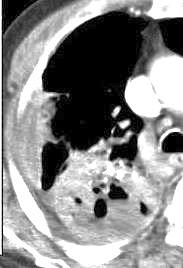

Tromboembolismo pulmonar.

Frecuencia del derrame:

Rx: 32%. TC: 47%

Unilateral. 85%

< 1/3 del hemitórax: 90%

Todos exudados

58% con eritrocitos

21% tabicación lo que causa demora en el diagnóstico

TEP. Empiema pleural. Atelectasia redonda

Porcel JM et al. Analysis of pleural effusions in acute pulmonary embolism: radiological and pleural fluid data from 230 patients. Respirology 2007/ Iguchi T et al. Desquamation of the subpleural lung parenchyma caused by empyema after pulmonary embolism: A case report. Respirol Case Rep. 2022 .